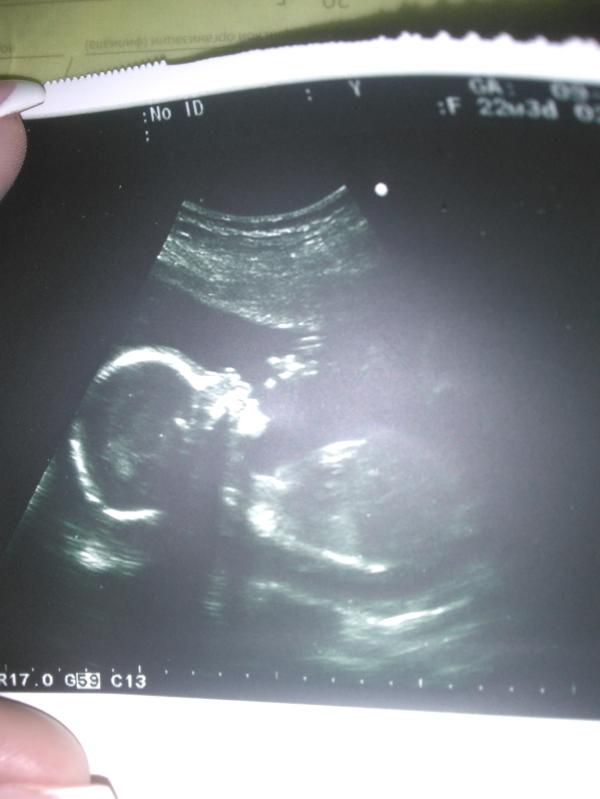

Сходила на УЗИ в 20 недель

И узнали что в 4 раз и опять #дочка хотели #сыночка но Бог дал дочку.